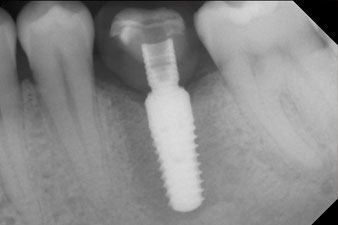

A first mandibular molar in a young patient had to be extracted due to extensive damage by caries with endodontic complications. Crowning the generally healthy neighbouring teeth could only be avoided with an implant. Six weeks after extraction, the alveolus proved to have insufficient bone. The implantation had to be combined with surrounding augmentation.

However, six weeks after the extraction incomplete ossification was found after preparation of the mucoperiosteal flap in the region of the former mesial alveolus.

The implant was placed as planned after thorough removal of the granulation tissue (blueSky, bredent).

The torque used for the machine-driven placement was 43 Ncm. In addition, after screwing a measuring post (SmartPeg) specially matched to the implant, the ISQ value was measured with the probe of the W&H Osstell ISQ module.

This module is an optional extra for the W&H Implantmed and is docked to the implantology motor (see Fig. 11). The dimensionless ISQ value immediately after insertion was 64 orovestibular and 68 mesiodistal (maximum value = 100).

These values could have indicated open healing or even immediate restoration. Due to the insufficient crestal bone volume at the implant, the region was augmented with the bone chips collected during preparation of the implant bed and sutured to exclude saliva.